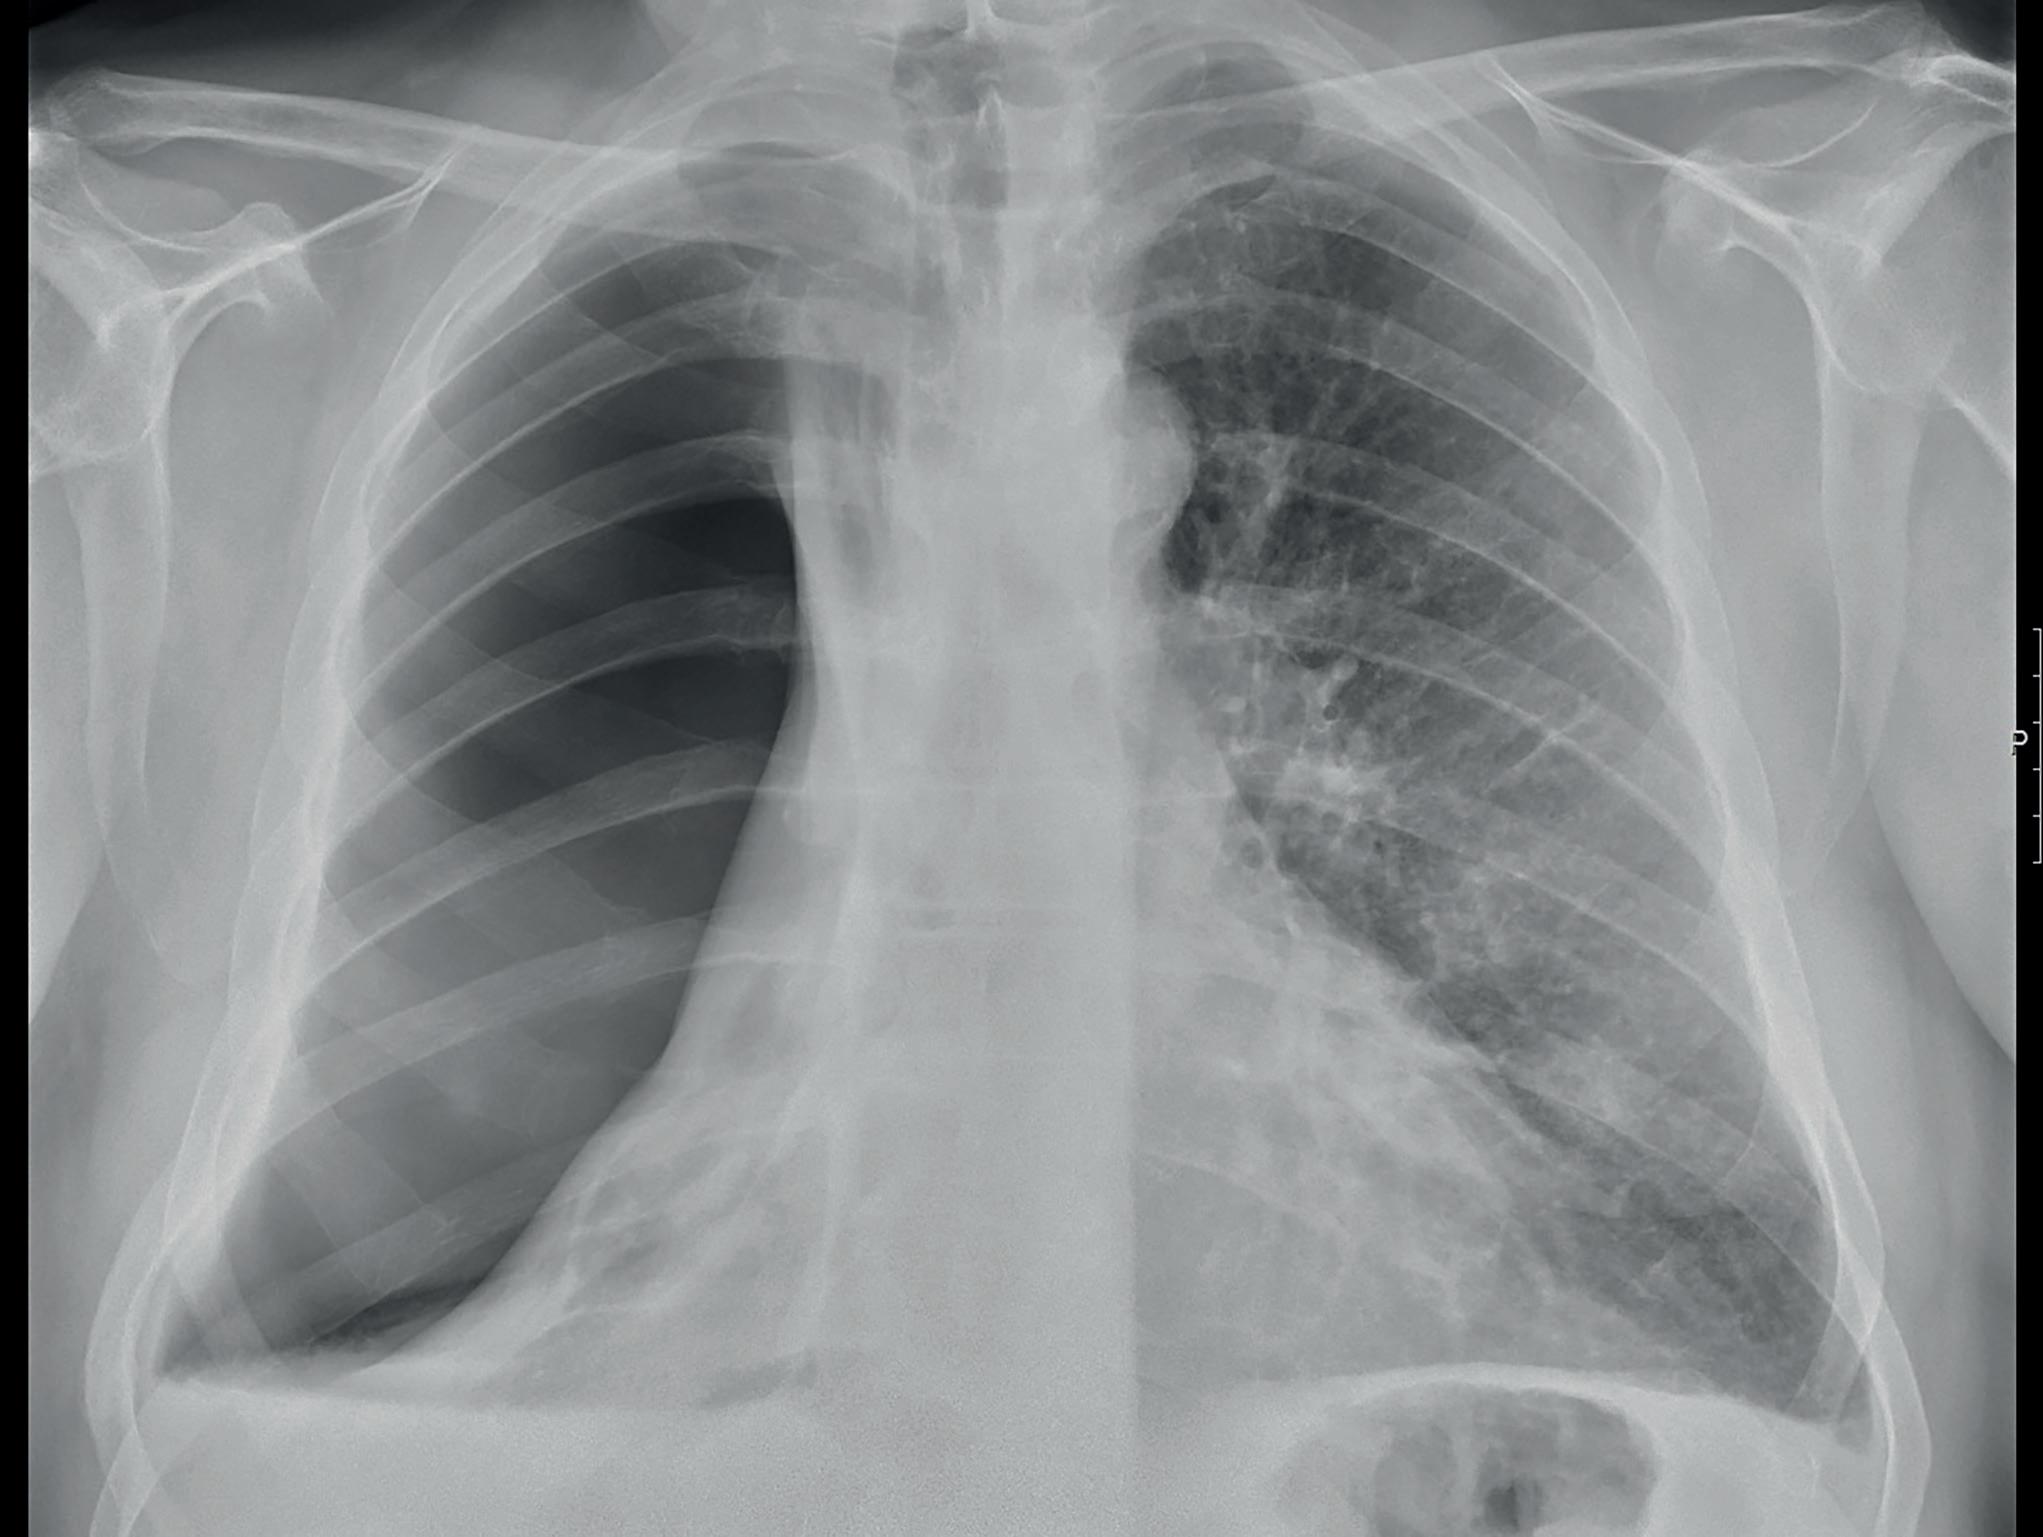

Pneumotoraks, punktert lunge, er definert ved tilkomst av luft fra lungen til pleurahulen. Ved spontan pneumotoraks er dette oppstått uten forutgående traume eller inngrep [1, 2]. Man har skilt mellom primær spontan pneumotoraks (PSP) hos de tilsynelatende lungefriske (oftest yngre, 15-30 år), og sekundær pneumotoraks (SSP) dersom det foreligger lungesykdom (oftere eldre, med KOLS/emfysem, CF, kreft eller kronisk infeksjon). Dette skillet er gjennomgående både for studier og toneangivende retningslinjer, men er nå omdiskutert da man også finner strukturell patologi hos de unge, lungefriske [3]. Pneumotoraks påvises oftest på klinisk mistanke ved røntgen toraks eller torakal ultralyd i øvede hender [4, 5]. Bilde 1. Stor pneumotoraks. Hvordan vil du behandle denne?